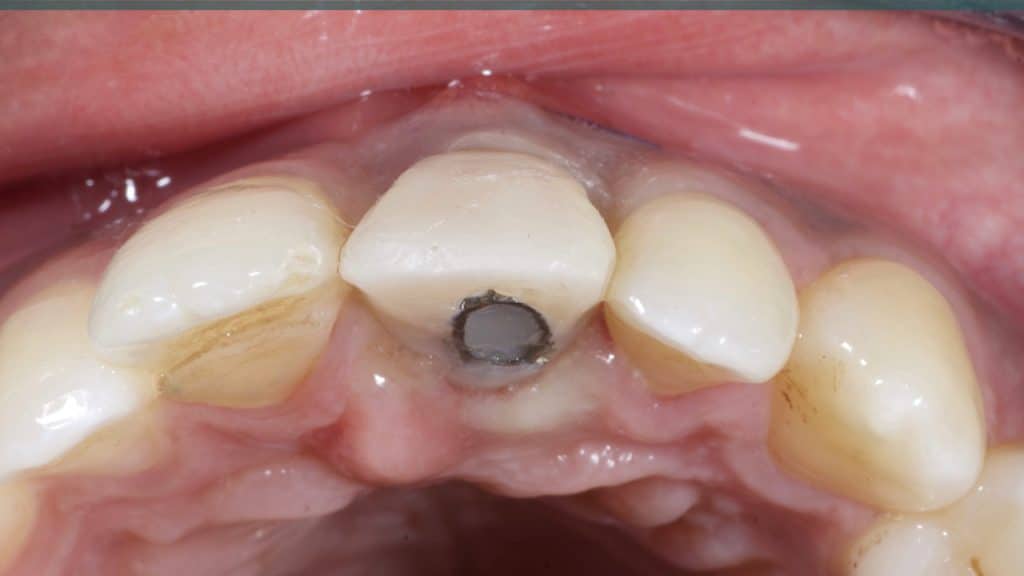

A 27-year female patient with dislodged Resin bonded FPD. She had that FPD for past few years, it had metal wings on palatal surfaces of UR1 and UL2 and a post like metal extension into the root canal of UL1. There was gingival abscess due to fractured root segment most probably due to extended metallic post like structure. Immediate implant placement (IIP) and Immediate restoration (IR) was planned for this patient.

Immediate post-op